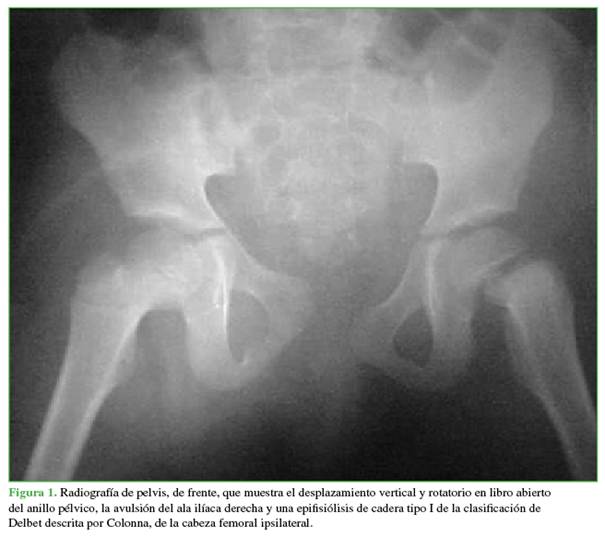

De todas las radiografías solicitadas la de pelvis de frente reveló fracturas compatibles con politraumatismo (Figura 1). Se observa una fractura de pelvis tipo C según la clasificación AO, más una avulsión del ala ilíaca y una fractura tipo A de la misma clasificación.1 En la epífisis femoral proximal izquierda, se constató una epifisiólisis tipo I (transepifisaria) según la clasificación de Delbet (Figuras 2 y 3).2